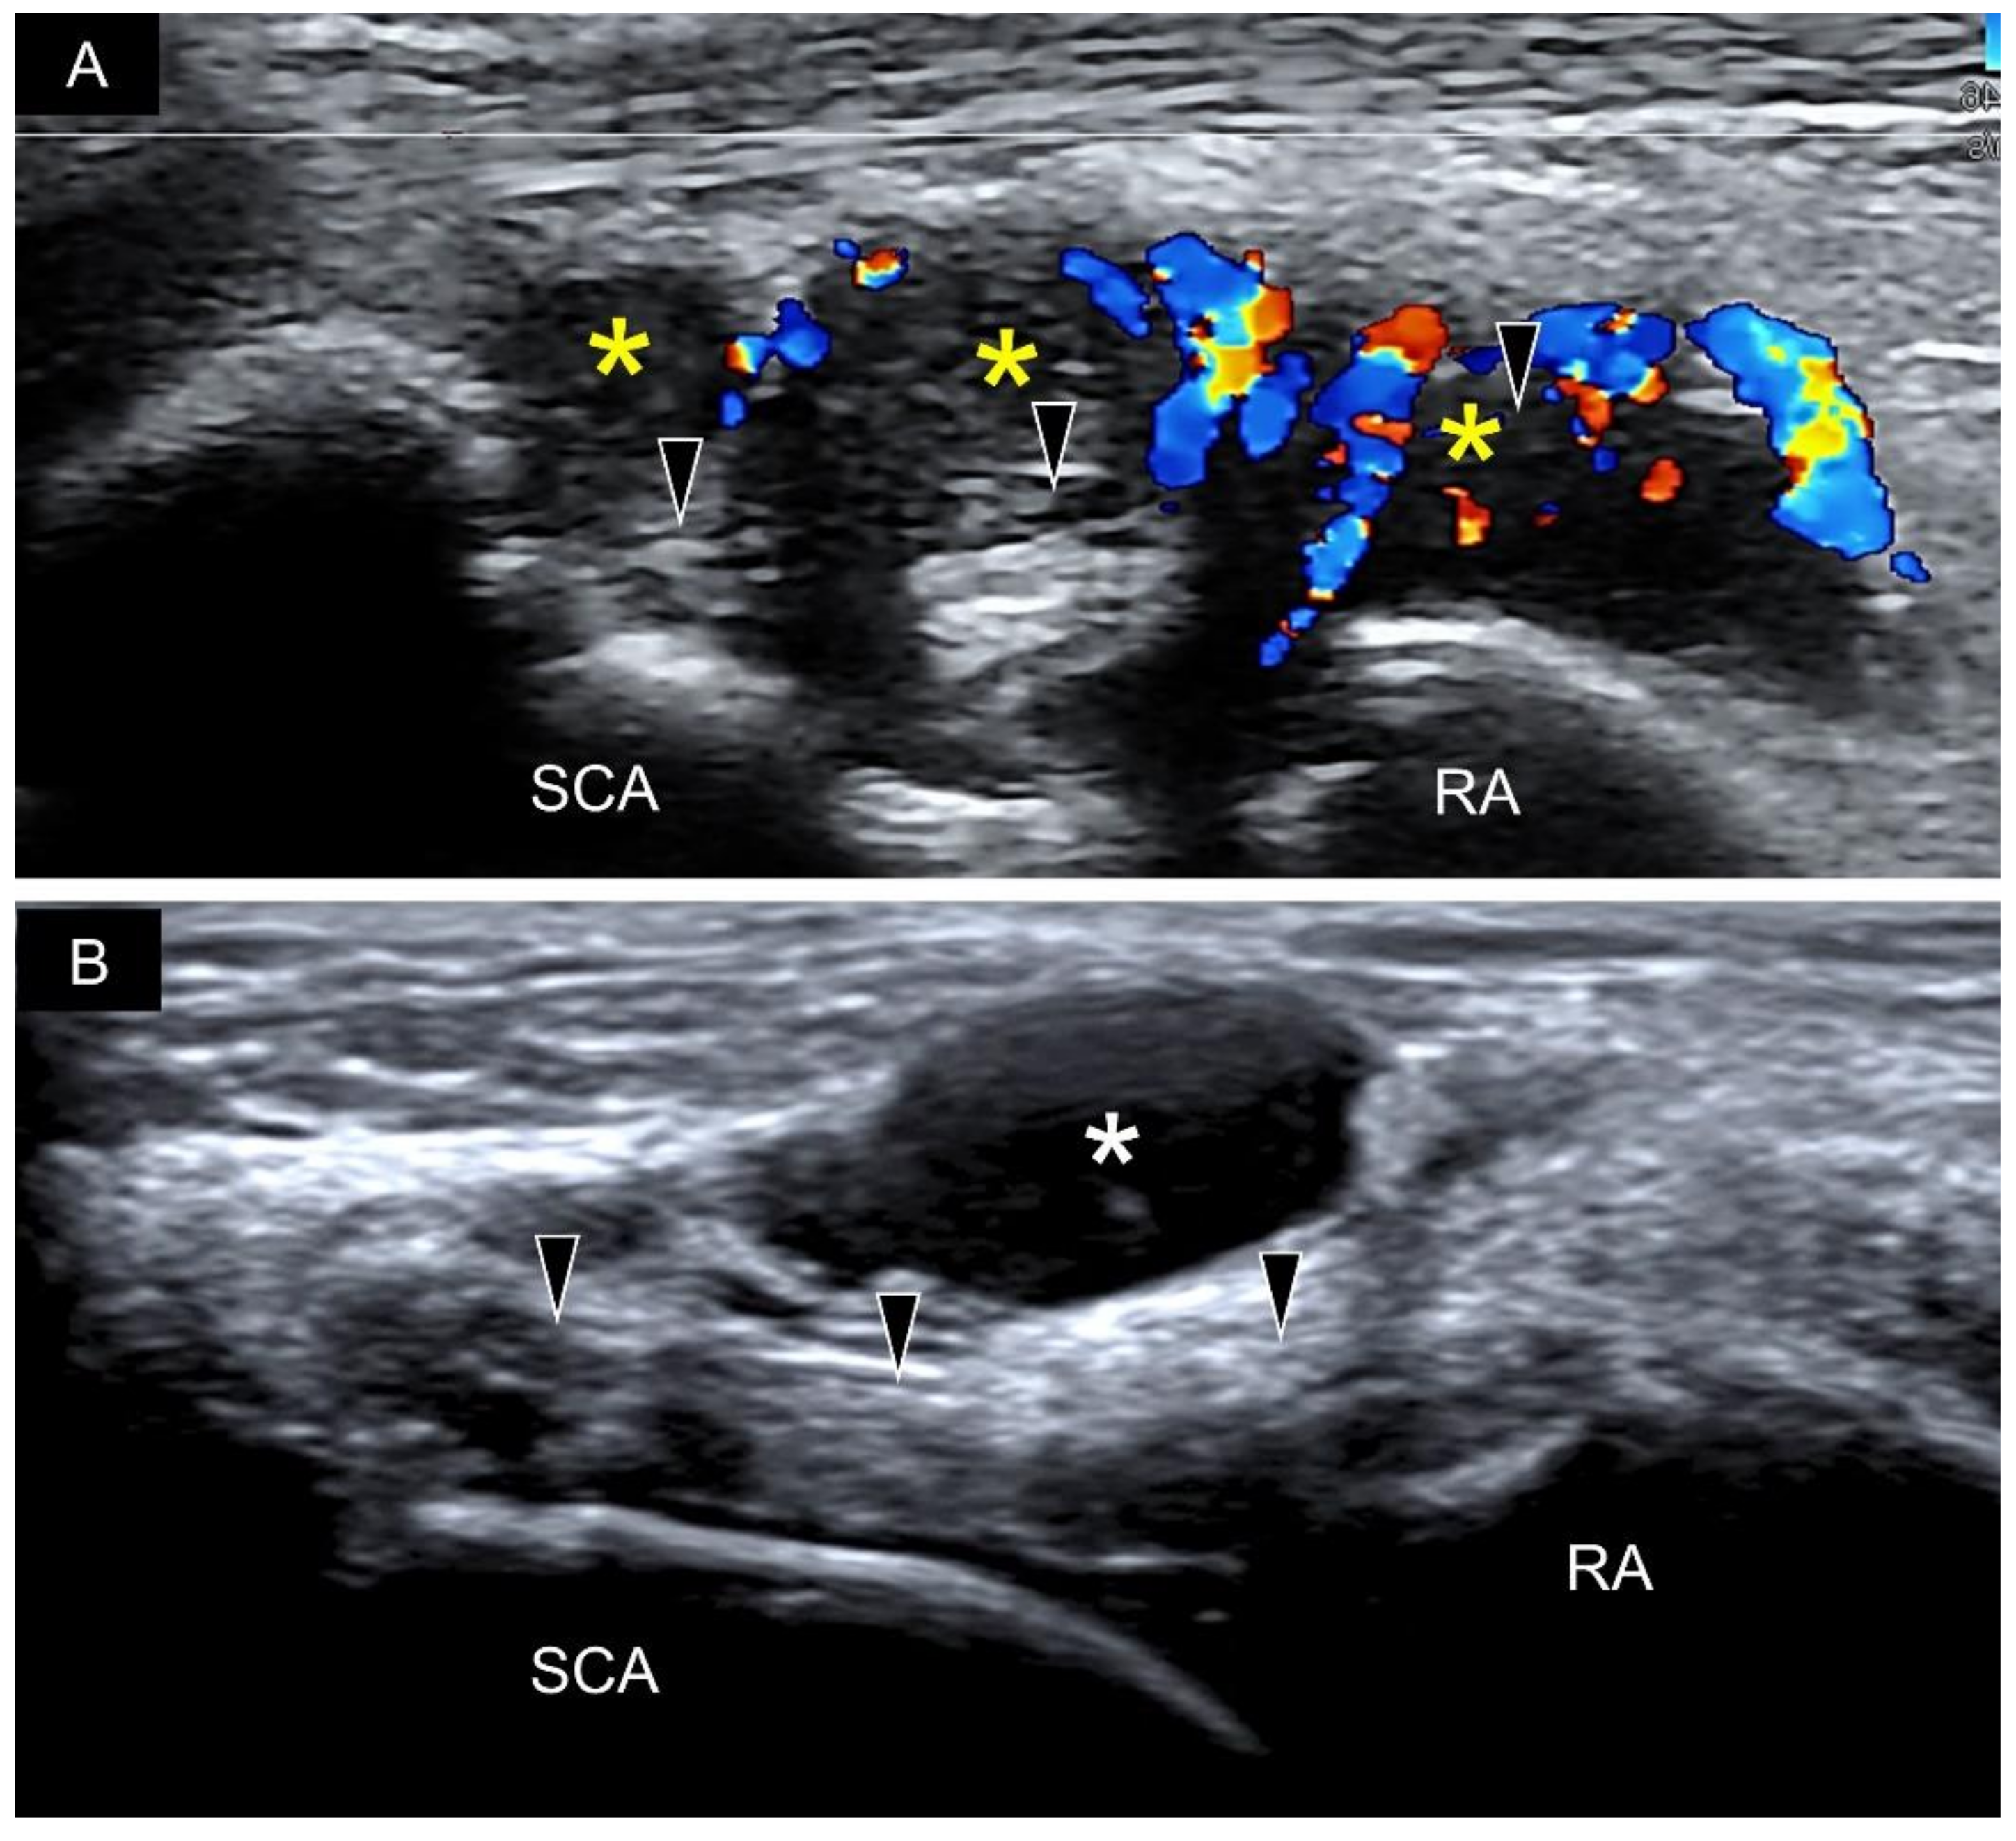

8. Pathology

3. Sonoanatomy of Volar Extrinsic Carpal Ligaments

4. Sonoanatomy of Volar Intrinsic Carpal Ligaments